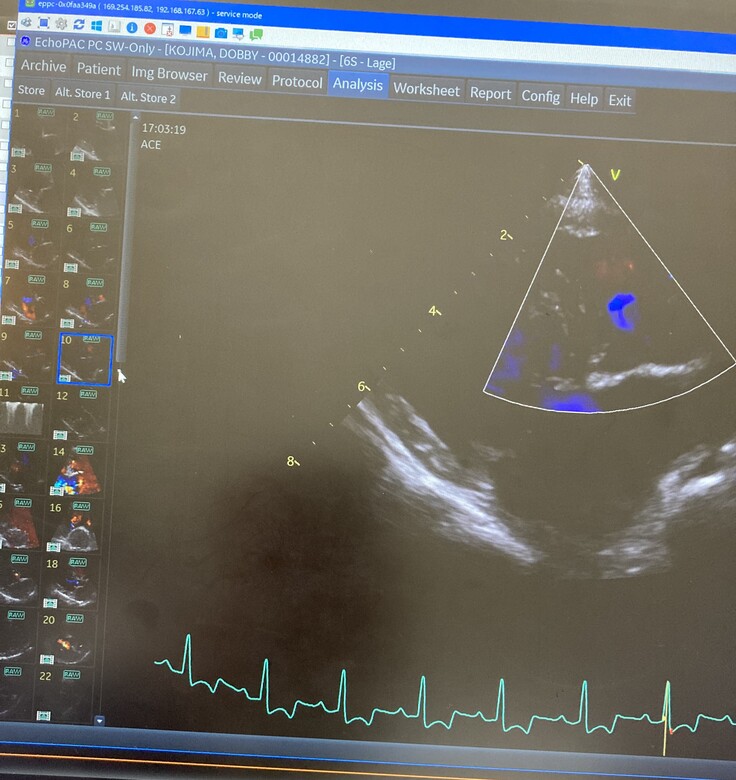

▼心臓のエコー画像

父親や兄と同じ病を患うドビーが、今現在では ステージC に入ってしまっており、酷くショックなことに

今回検査を受けた手術先の病院で、「8ヶ月をめどに見ておいてください。」と余命宣告をされました。

ドビーの場合は、僧帽弁が数カ所”切れてしまっている状態”らしく、

今は心臓が、めいっぱいの状況で頑張ってくれているそうなのです。